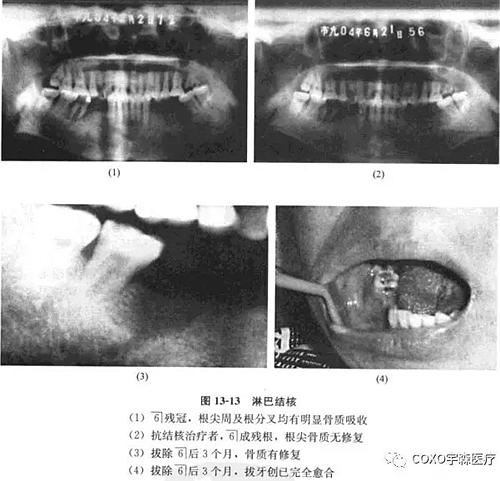

經(jīng)右頜下淋巴結(jié)穿刺,見上皮細胞、多核巨細胞和淋巴細胞,結(jié)合臨床及6]近中原切片,認為病變符合結(jié)核診斷。行抗結(jié)核治療,3個月后復查,臨床頜下淋巴結(jié)顯著縮小,口內(nèi)牙齦腫脹基本消失,無任何創(chuàng)面,殘冠已折斷,僅剩6]殘根,X線示根尖周骨質(zhì)無修復現(xiàn)象。遂拔除司殘根,繼續(xù)行抗結(jié)核治療,3個月后骨質(zhì)有修復,拔牙創(chuàng)已完全愈合(圖13-13)。